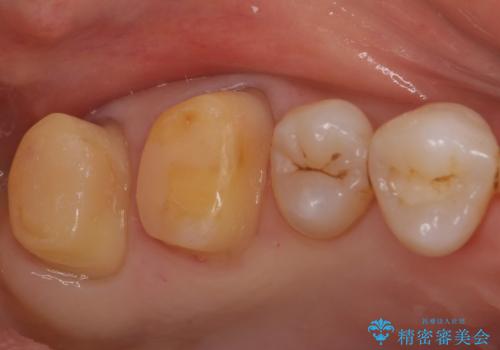

- 銀歯を白くしたいとのことで来院されました。

銀の詰め物を除去した後、その奥にある古い詰め物も除去し完全にむし歯を取り切ったことを確認してからセラミッククラウンを装着していきます。